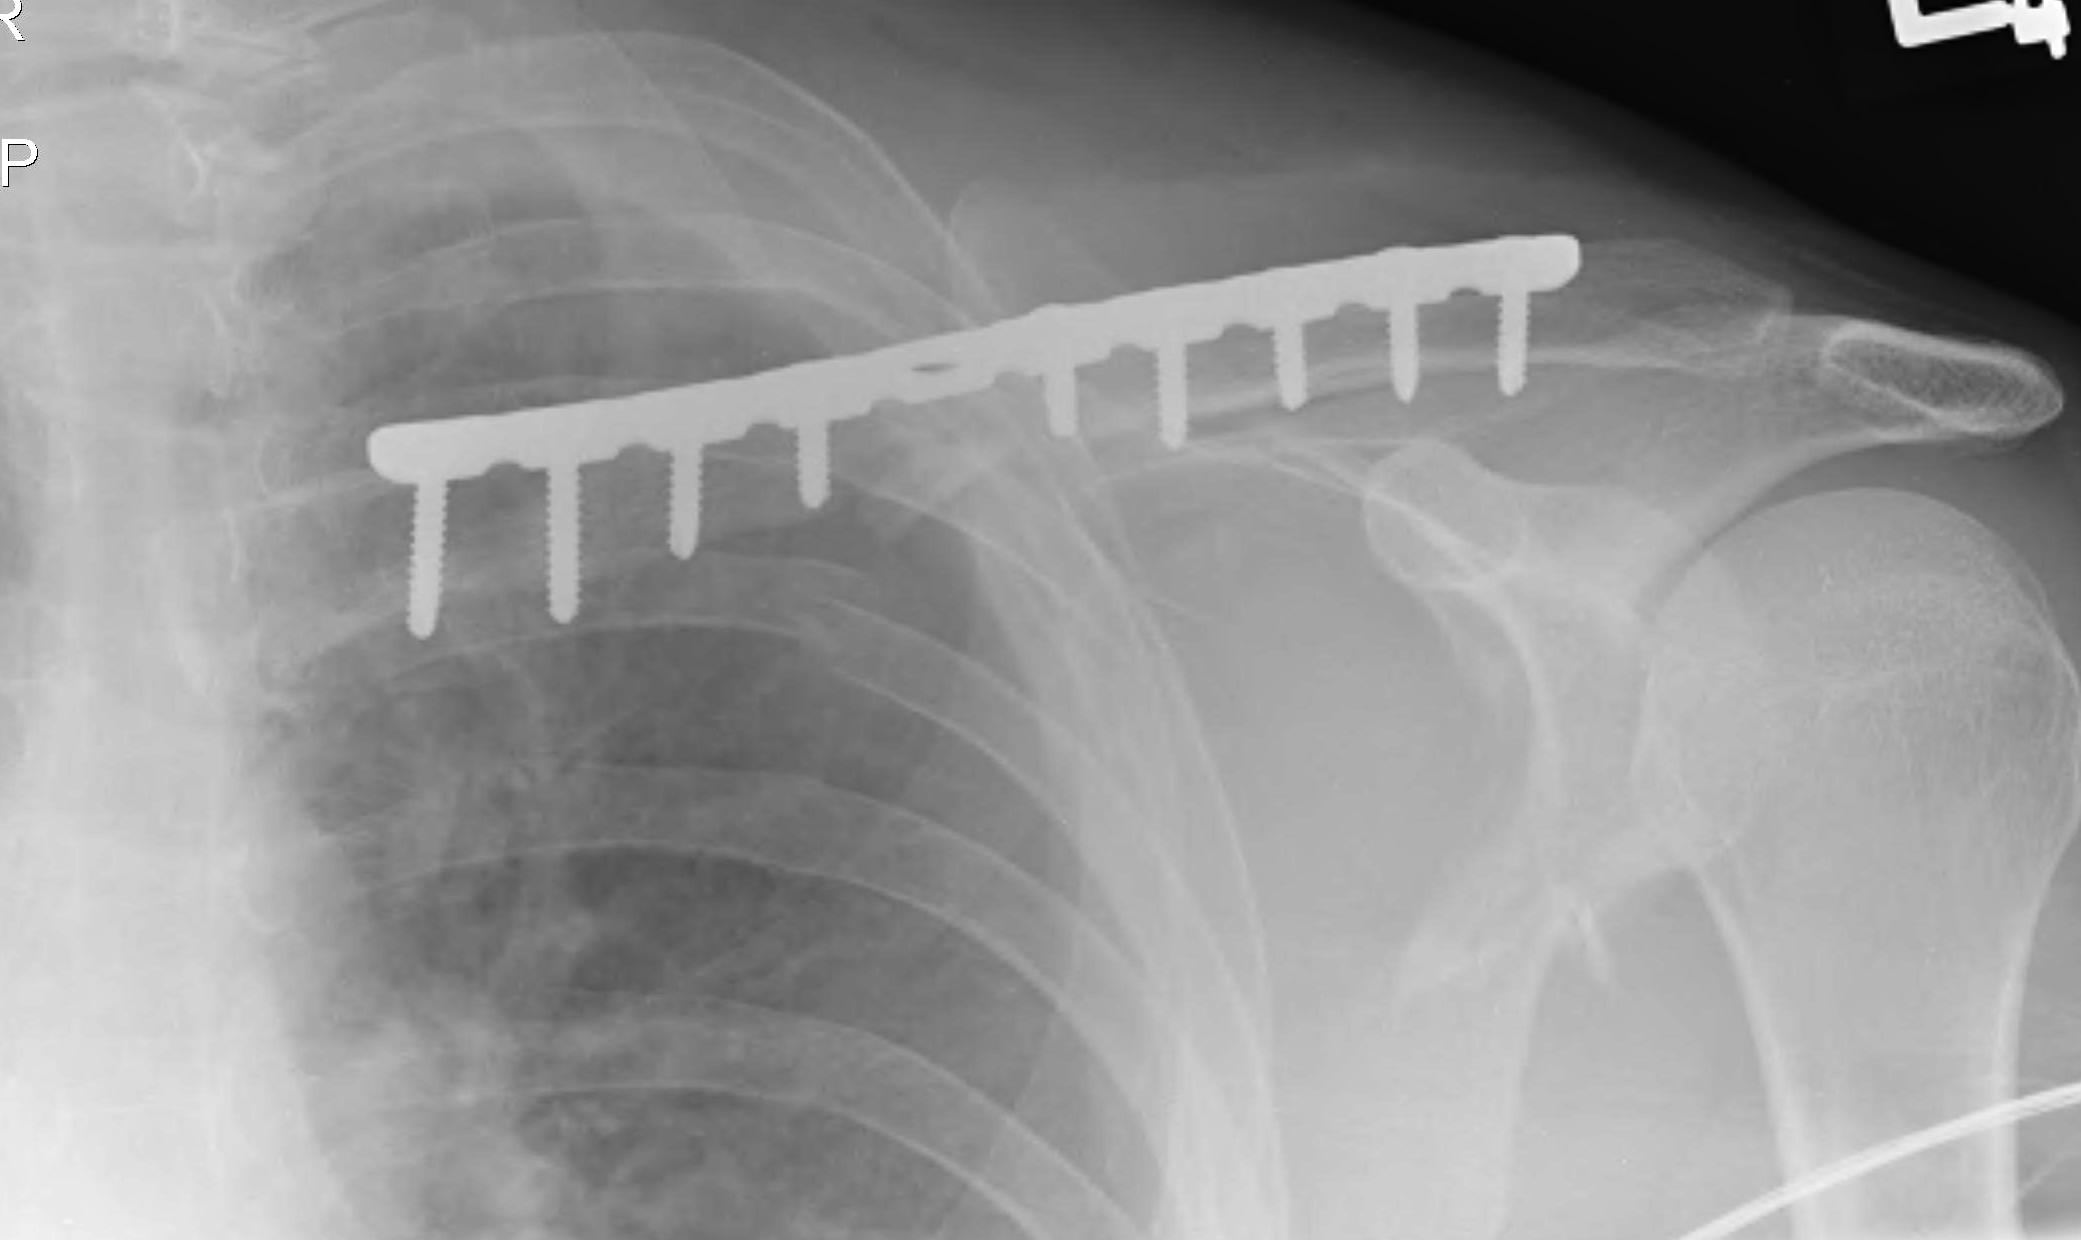

ORIF clavicle

Minimally displaced glenoid fracture

Floating ShoulderFloating Shoulder Clavicle ORIF

floatfloatFloat